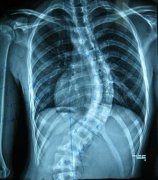

强直性脊柱炎是一种脊柱的慢性进行性炎症。主要是以侵犯脊柱关节 ...